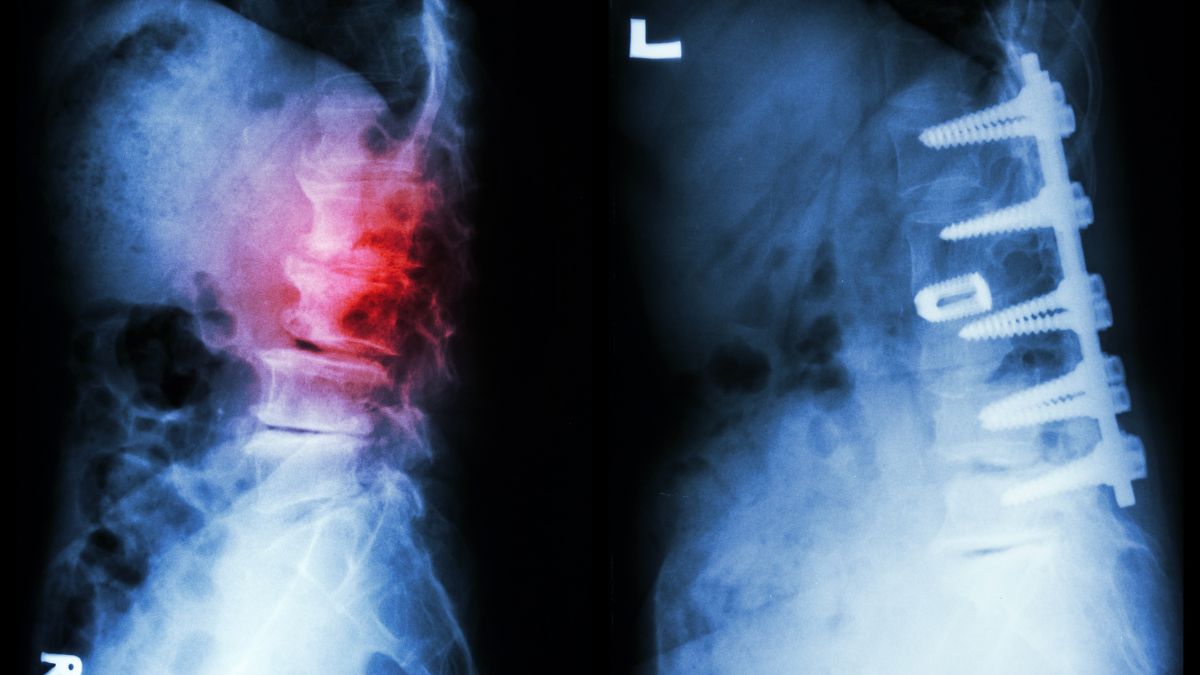

Dr Chhabra defined, “Spondylolisthesis is a condition where a vertebra in the spine slips forward out of place relative to the vertebra below it. This can happen due to a stress fracture in a part of the vertebra called the pars interarticularis. This stress fracture, known as spondylolysis, often precedes spondylolisthesis, especially in children and adolescents.”

Dr Chhabra said, “Imaging tests, such as X-rays or MRI scans, can confirm the diagnosis and determine the severity of the slippage.”

In rare instances, where the slippage is severe or causes neurological problems, surgery might be necessary to realign the vertebrae and prevent further complications.